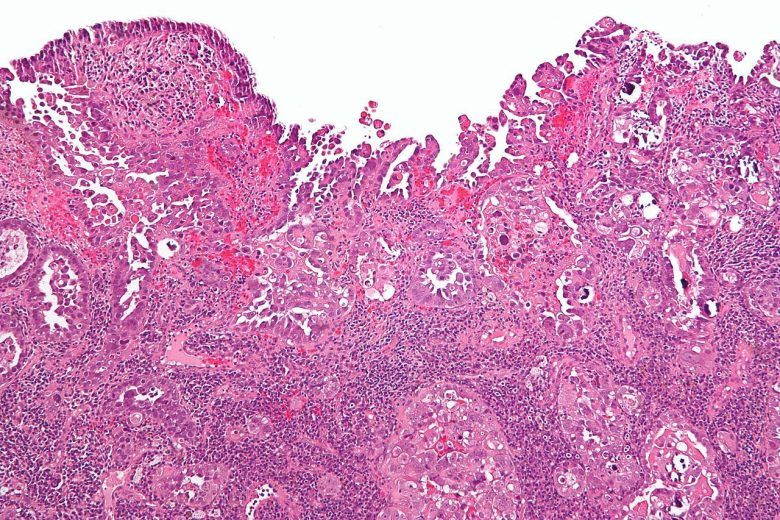

Pancreatic cancer

“Pancreatic cancer can develop from two kinds of cells in the pancreas: exocrine cells and neuroendocrine cells, such as islet cells. The exocrine type is more common and is usually found at an advanced stage. Pancreatic neuroendocrine tumors (islet cell tumors) are less common but have a better prognosis.”

Image Credit: Nephron / Wikimedia Commons.